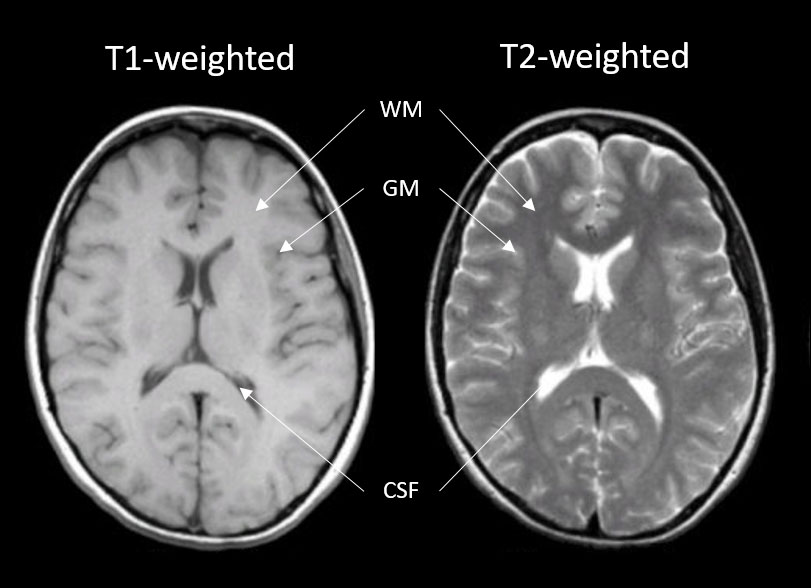

Generally, T1 and T2 weighted images are the most common (Fig. 2). On a T1-weighted scan, tissues with high water content will have lower signal (appear dark; e.g., cerebral spinal fluid [CSF]) and tissues with higher fat and paramagnetic substances will have higher signal (appear lighter; e.g., gray [bundles of neural cell bodies] and white matter [bundles of neuronal axons]). T1 images are great for demonstrating anatomy. On a T2-weighted scan, compartments filled with water (such as CSF compartments) appear bright and tissues with high fat content (such as gray and white matter) appear dark. This is good for demonstrating pathology since most, but not all, lesions (damaged tissue) tend to develop edema and are associated with an increase in water content.

Figure 2. Left: T1-weighted image of a brain; Right: T2-weighted image of the brain. Images highlight contrast differences of the various tissue types (white matter [WM], gray matter [GM], and cerebral spinal fluid [CSF]) being interrogated.